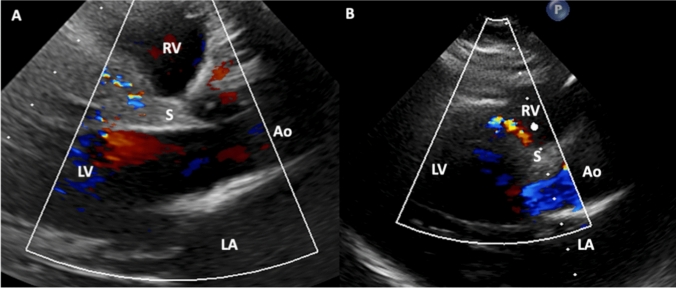

A 39-year-old women with newly diagnosed ALCAPA syndrome during pregnancy.